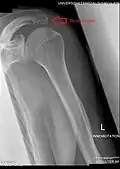

Radiograph of the shoulder showing an os acromiale